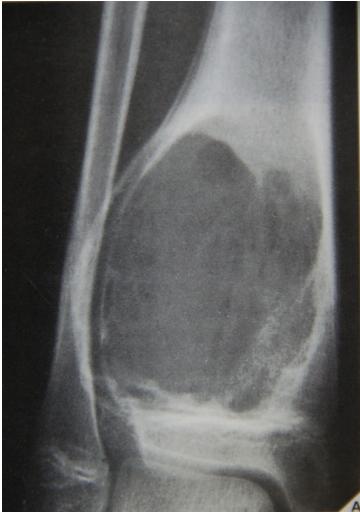

site: Distal shaft of femur size: matrix: Opaque, well defined, ossifying fibroma soft tissue involvement: no peristeal reaction

Could be malignant, even though no periosteal reaction, may be due old fracture

Pathological fracture, after metastasis